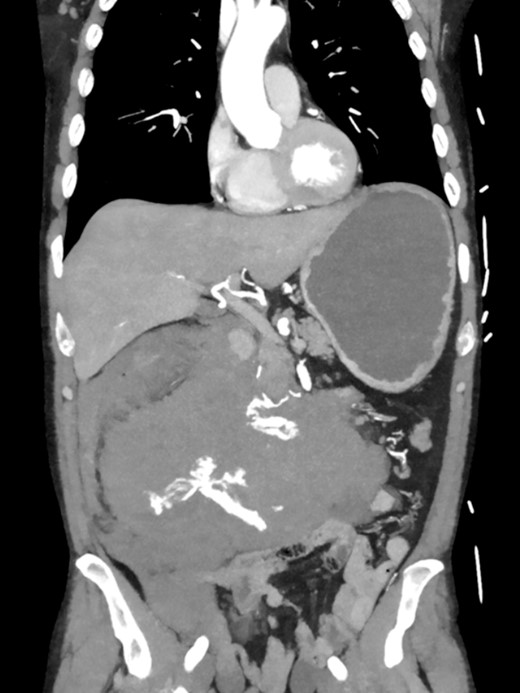

Postoperatively, the patient achieved hemodynamic stabilization in the intensive care unit. On the sixth postoperative day, there was a recurrence of circulatory collapse in addition to relevant bloody discharge through the drains. CT imaging once again revealed an active bleeding of the pancreaticoduodenal artery, which was successfully treated interventionally using coiling (Figs 2 and 3).

Angiography revealing the aneurysm of the pancreaticoduodenal arcade.